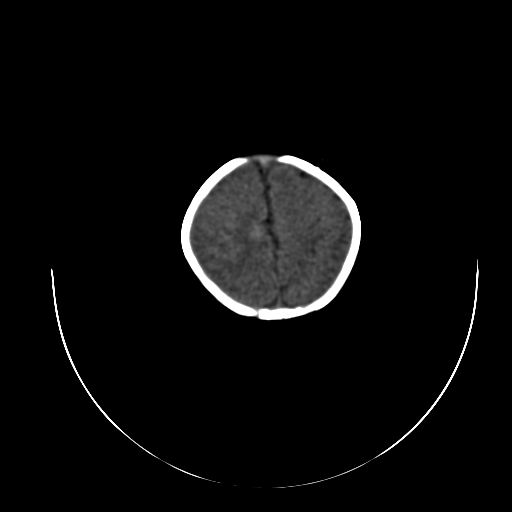

标题: PED0840:女,1.6岁,全身粘膜黄染6天,医生考虑新生儿胆红素 [打印本页]

标题: PED0840:女,1.6岁,全身粘膜黄染6天,医生考虑新生儿胆红素

正常  机器伪影

双侧脑实质多发低密度灶;是图象燥声?烟雾病?         右基底节到顶叶高密度灶,长轴大于宽度,伪影?出血灶??

机器伪影,每层都有,如果是病灶那不成了园柱形的了吗

每层都有且没有改变,应该是机器伪影。

谢谢拉,经过第二次扫描,就没有看见了,

开始我们也怀疑是机器伪影,但又怕是其他的。

不敢下结论。